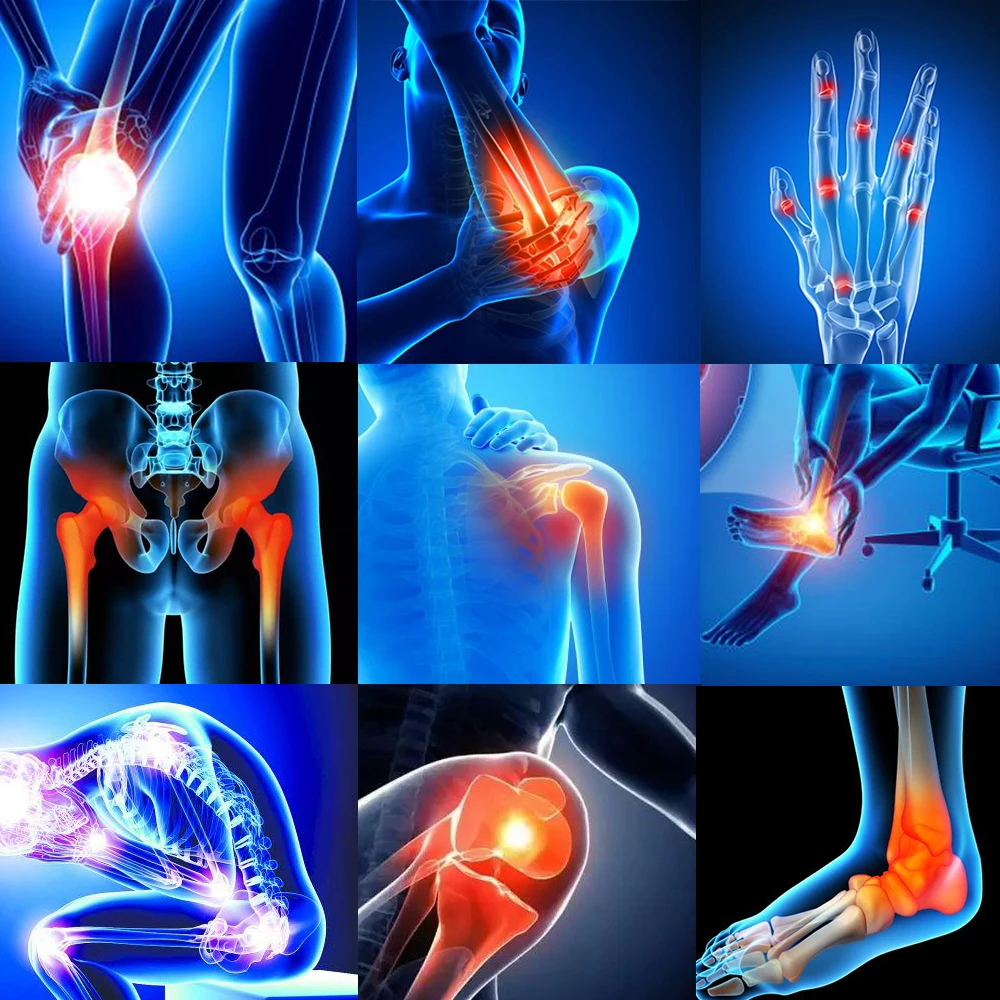

8pcs Medical Muscle Pain Patch, Arthritis, Osteochondrosis, Joint Pain, Bruises, Pain Relief Plaster Medical Patch D022